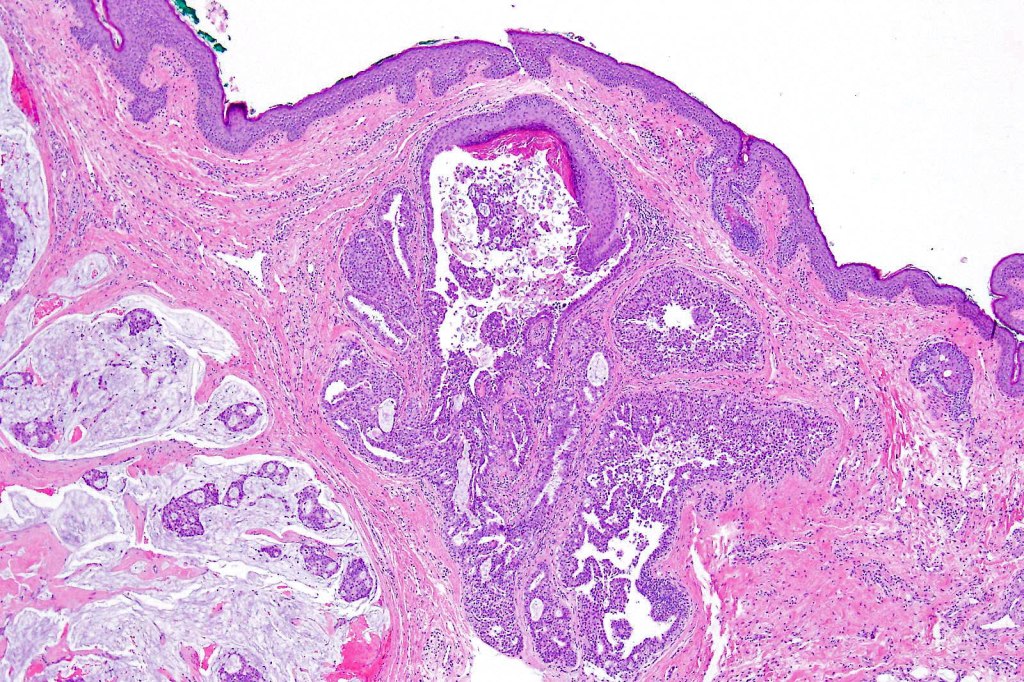

Endocrine mucin-producing sweat gland carcinoma & mucinous carcinoma are intrinsically linked. Indeed it is very likely that the former represents a pecurser to the latter. Very frequently an example shows histological features of both lesions (50% of cases).

Histological features

•Mucinous carcinoma is characterized by epithelial islands dispersed in a rich mucinous stroma

•EMPSGCa– multiple nodules of uniform epithelial cells with vesicular nuclei & small nucleoli

•In situ component sometimes evident

•Cyst formation sometimes evident

•Papillae & cribriform pattern sometimes evident

•+/- invasive mucinous carcinoma (50%)